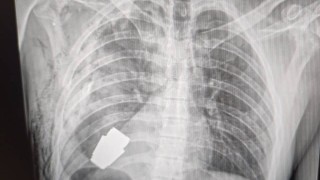

Лекари успешно извадиха пластмасова свирка заседнала в белия дроб на

...... Лекари успешно извадиха пластмасова свирка, заседнала в белия дроб на 3-годишно момиченце от град Санта Роса дел Агуарай в Парагвай.